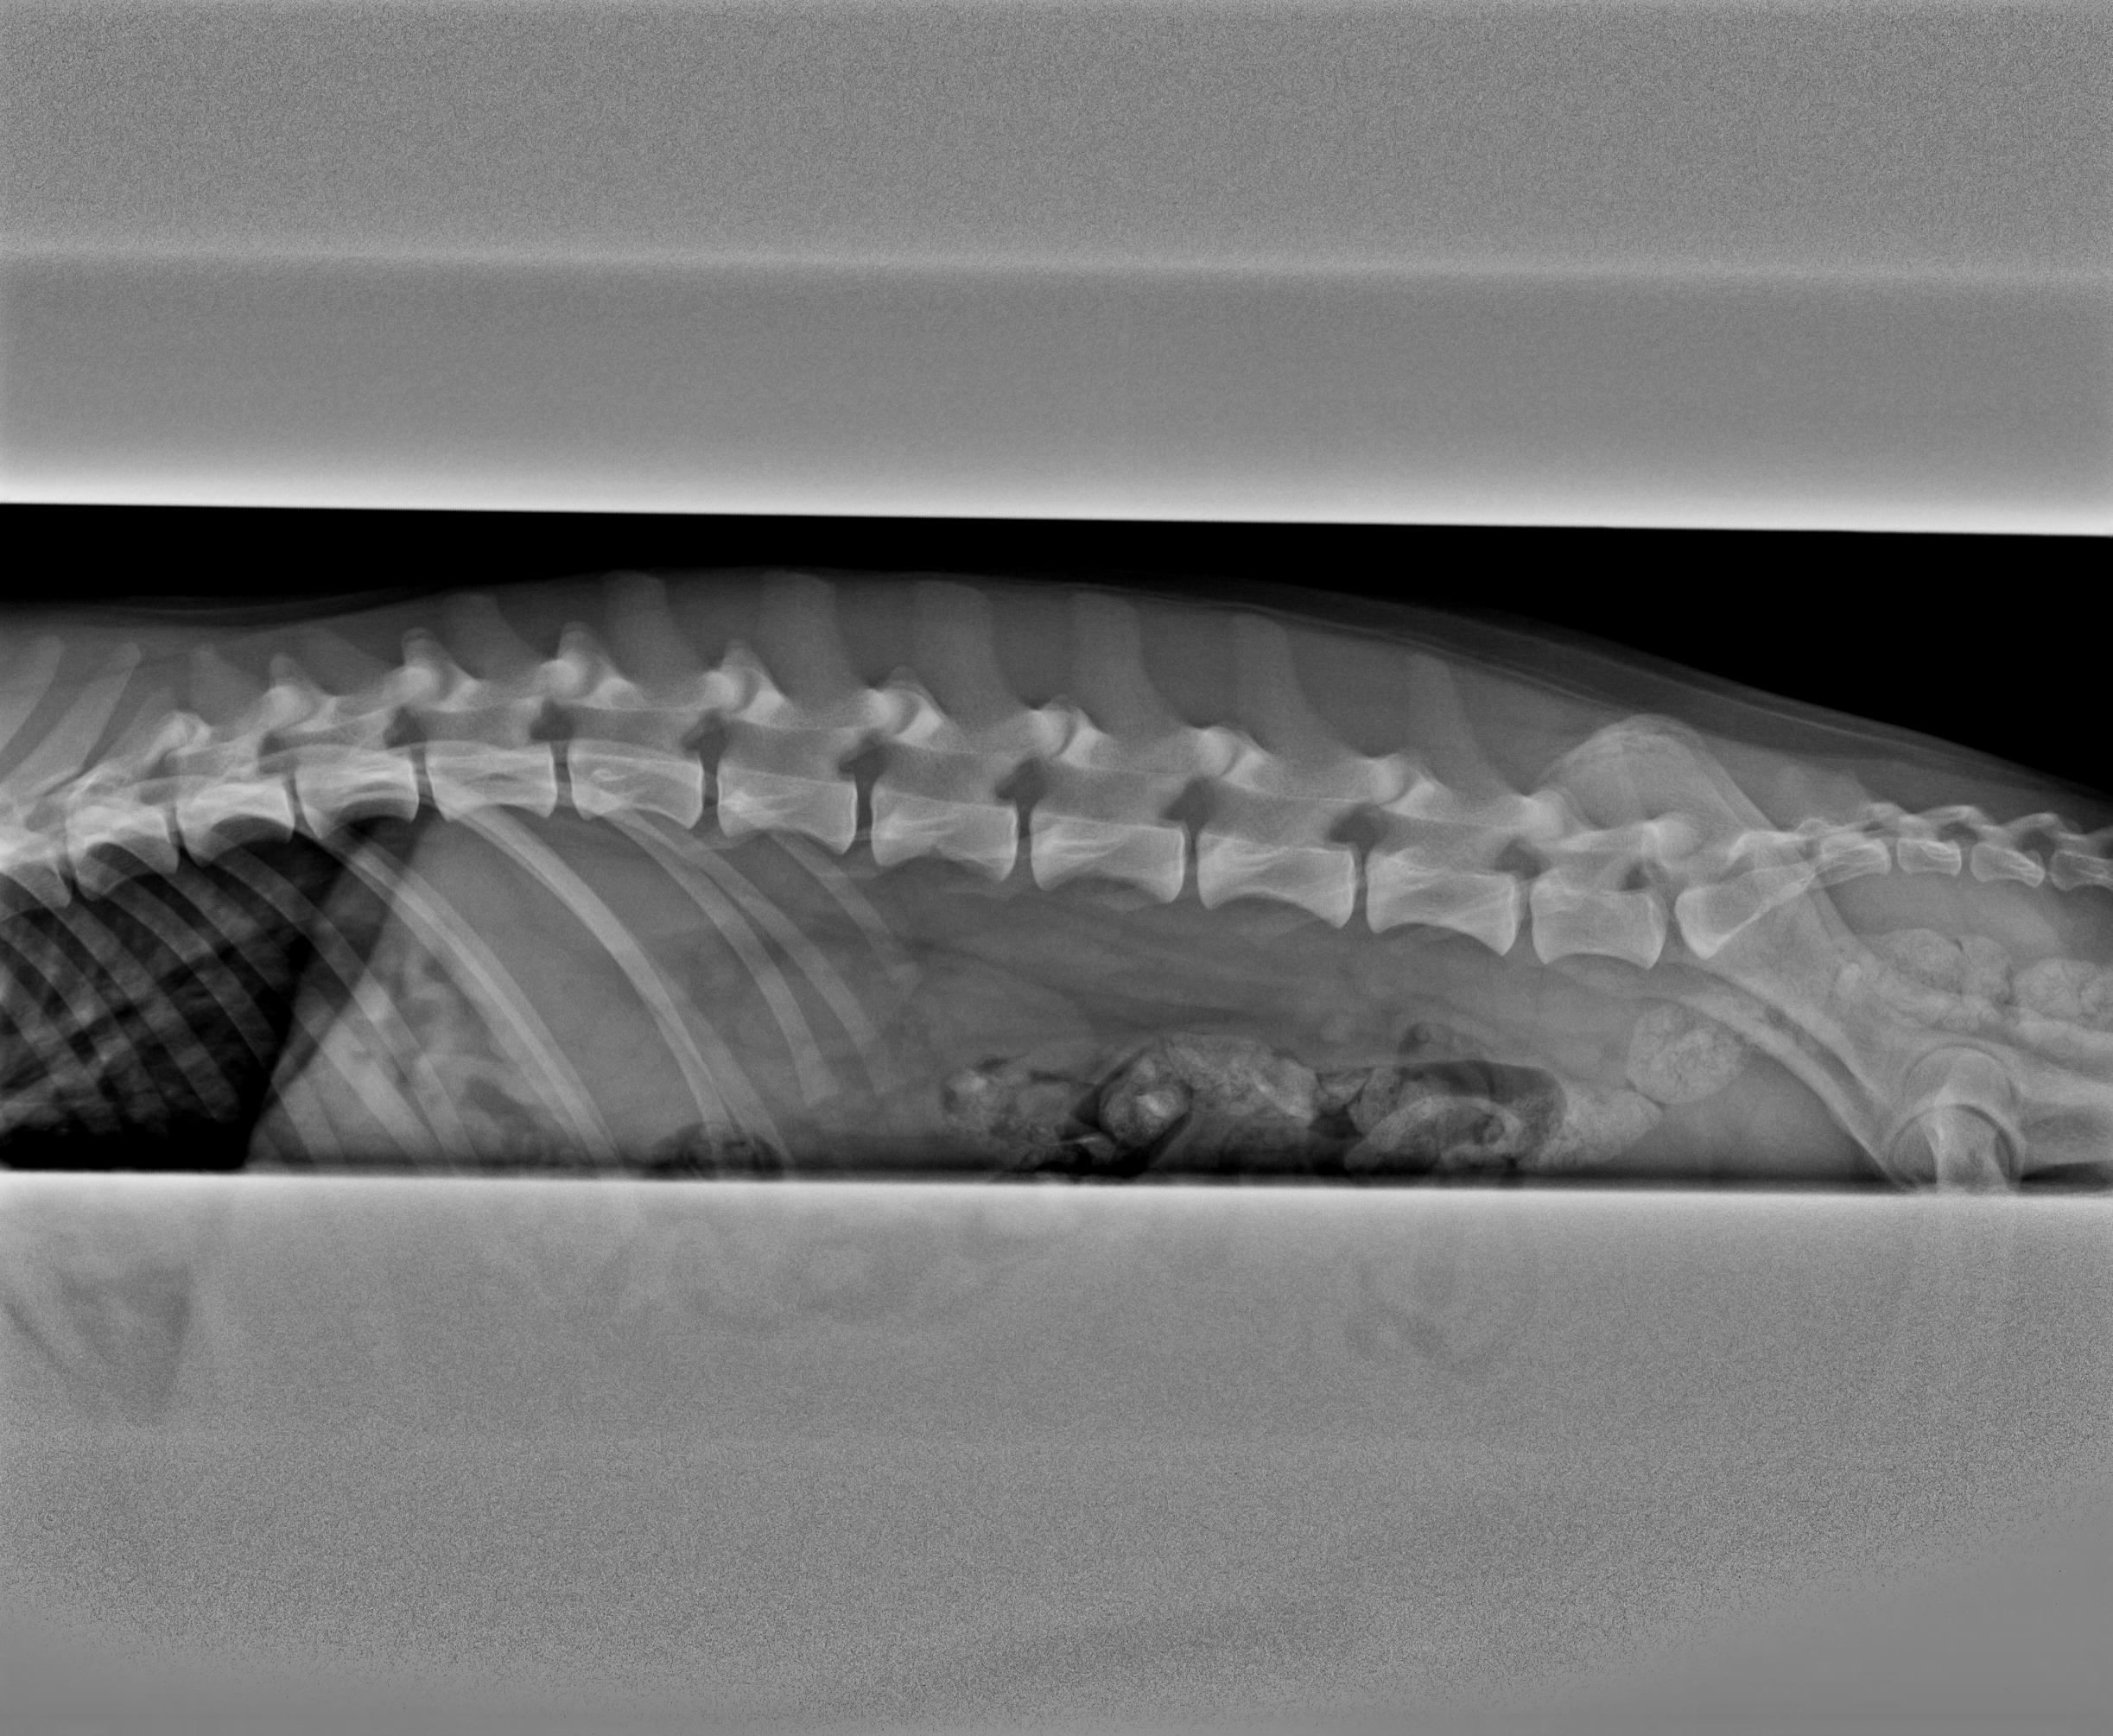

Sen sövdes han med en spruta i en muskel som han inte verkade känna och somnade mycket snabbt. Jag var med och höll i framdelen när han röntgades. Bilder togs på höfter, armbågar och rygg samt att ortopeden kände på knäna och svansen. Svansen bad jag honom känna på då den inte är helt rak i vissa lägen men han tyckte att det var så lite att det inte var något att bry sig om. Knäna var helt som de skulle så patella är UA.

När bilderna var tagna så fick Helix en uppvakningsspruta och sen gick vi och kollade på bilderna som han gick igenom väldigt noggrant. Överlag såg det helt normalt ut, något grundare skål på höger höft och en liten ”trappa” på ena armbågen, inga förändringar på leden så han trodde inte att det var något särskilt. Han kollade även på knäna på höftbilderna för att utesluta att höger knä skulle vara problem som orsakade muskelömheten men det såg helt normalt ut. Ländryggen hade rätt antal kotor och såg normal ut i övrigt.

Bilderna: